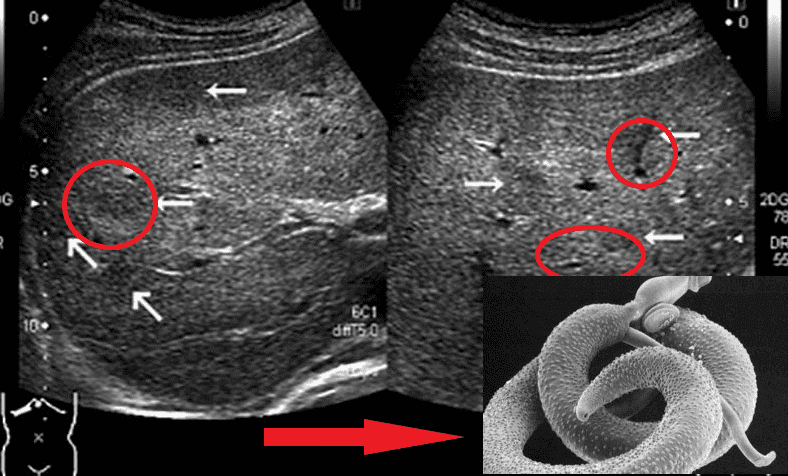

На фото нижче можете побачити знімок кишечника. Пацієнтка померла від раку кишківника, спричиненого паразитами. Паразити отруюють здорові клітини своїми токсинами, через що вони змушені перероджуватися, змінювати свою структуру. І перероджуються вони саме в ракові клітини, які агресивніші й здатні протистояти паразитам. Але для людини ці клітини згубні. Пухлина швидко розвивається і метастазує. Людина гине протягом лічених місяців.

"Ходи" паразитів у просвіті кишечника